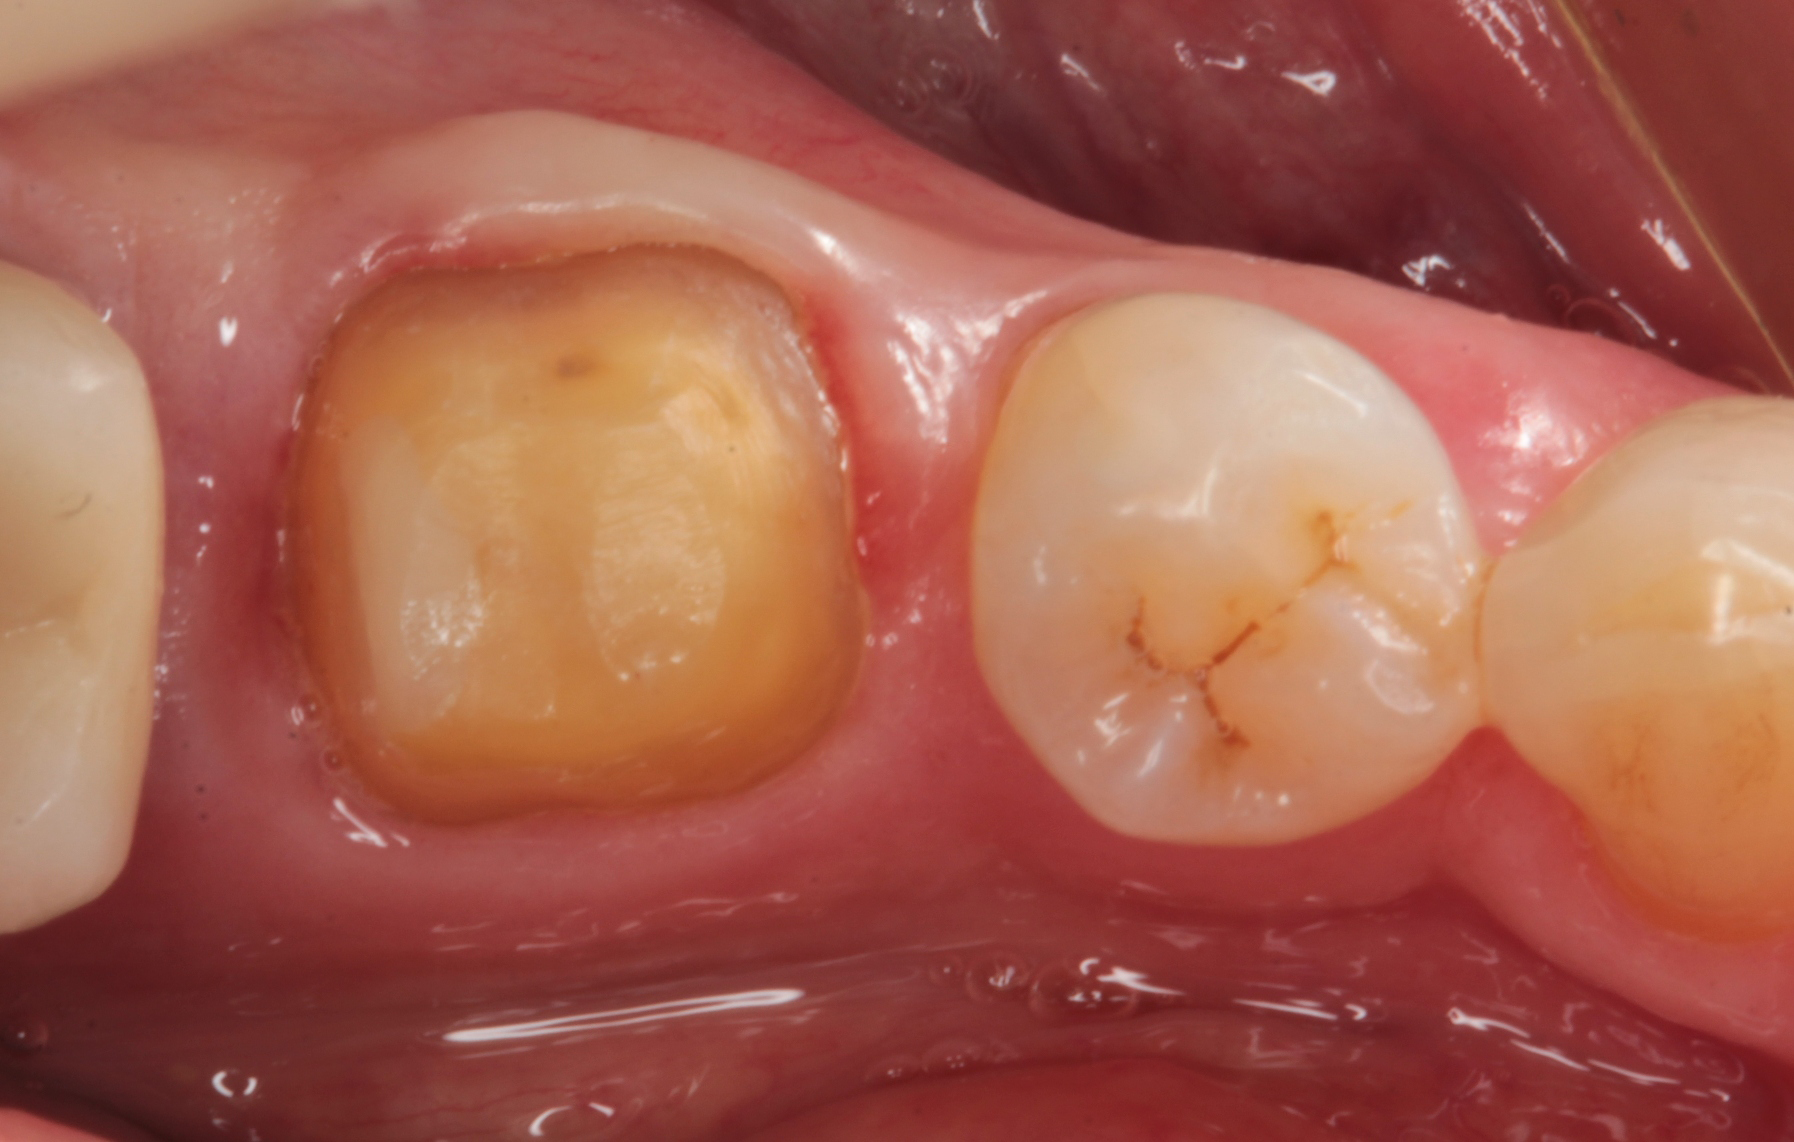

In Figure 3, you can see a close up view of the final impression taken with BONASCAN impression material. A light body was used to express around the margins and a heavy body was placed in the impression tray and seated directly over the light body. After five minutes, the impression was removed and evaluated. A provisional crown was fabricated and the patient was reappointed for seating.

Fig. 1 Fig. 2 Fig. 3